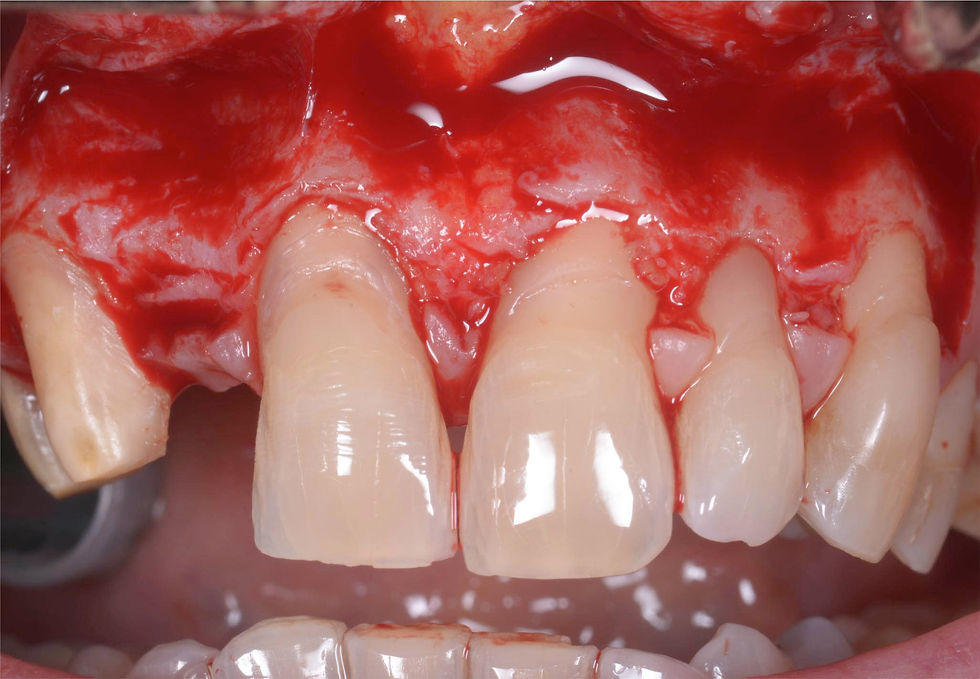

Full thickness flaps opening preserving the papillae, which will allow a coronal repositioning of the parabolas of the elements 1.1 and 2.1, in addition to the exposure of the bone available for the implant site preparation.